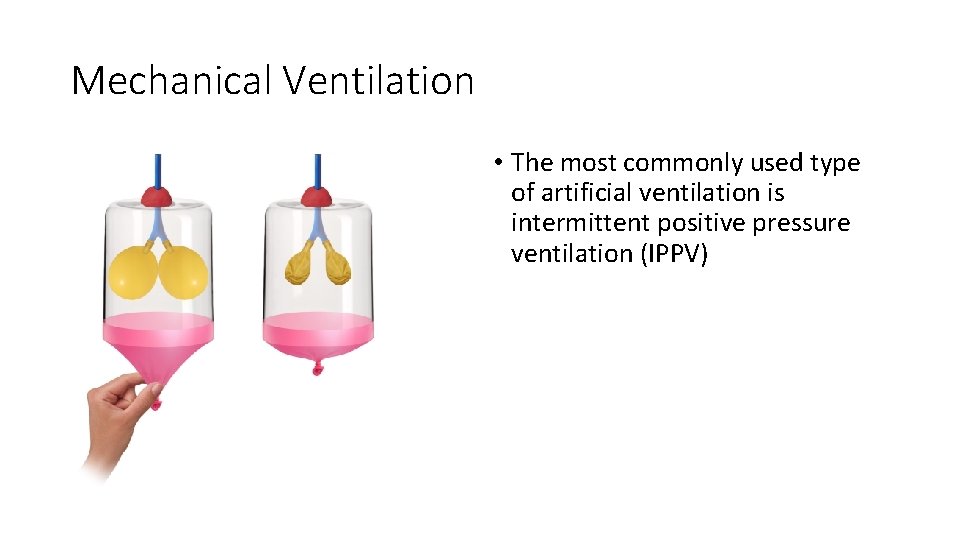

Mechanical Ventilation • The most commonly used type of artificial ventilation is intermittent positive pressure ventilation (IPPV)